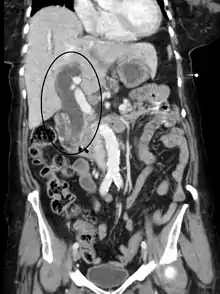

Biliary-tract dilation due to obstruction as seen on CT scan (frontal plane)

Most people presenting with jaundice have various predictable patterns of liver panel abnormalities, though significant variation does exist. The typical liver panel includes blood levels of enzymes found primarily from the liver, such as the aminotransferases (ALT, AST), and alkaline phosphatase (ALP); bilirubin (which causes the jaundice); and protein levels, specifically, total protein and albumin. Other primary lab tests for liver function include gamma glutamyl transpeptidase (GGT) and prothrombin time (PT).[36] No single test can differentiate between various classifications of jaundice. A combination of liver function tests and other physical examination findings is essential to arrive at a diagnosis.[37]

Medical imaging such as ultrasound, CT scan, and HIDA scan are useful for detecting bile-duct blockage.[40]